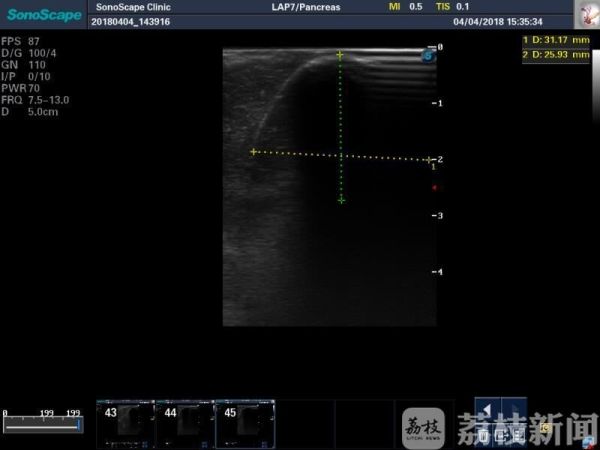

昨天(4月4日),南医大二附院胰腺中心在B超、麻醉等多名医务人员的协助下,首次成功完成了两例腹腔镜下进展期胰腺癌冷冻消融手术(LAHC)。据悉,这是该院胰腺中心团队在原有胰腺癌冷冻治疗基础上又一技术性突破,使治疗更精准,更直观,更微创,在不增加患者创伤的前提下,达到最佳治疗效果。

南医大二院胰腺中心一位医生介绍:“进展期胰腺癌生存时间最长患者已有一年余,至今存活。”氩氦刀冷冻消融技术的引入,填补了胰腺肿瘤局部消融治疗的空白,联合手术技术和放化疗等杭肿瘤治疗方法,我中心结合自己经验,制定了胰腺肿瘤综合治疗的个体方案,力求使任何病期的胰腺癌患者都能得到最有效的治疗。

目前,冷冻消融技术已经取得初步成果。在去年,该院胰腺中心就先后完成各类氩氦刀冷冻消融治疗共54例,手术操作均顺利,术后恢复满意,无严重并发症。